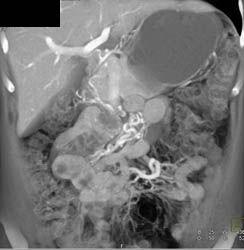

Focal Nodular Hyperplasia (FNH)